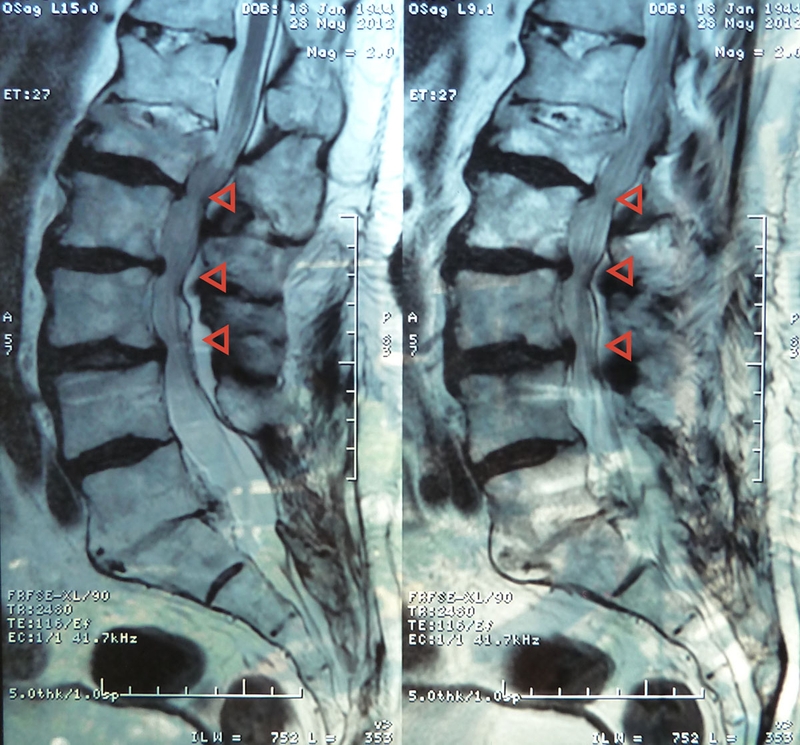

Gai cột sống (thoái hóa cột sống), là một quá trình tự nhiên trong cơ thể xảy ra khi lớp sụn khớp dần mòn do tác động của thời gian và tuổi tác. Khi các đầu xương đốt sống không còn được bảo vệ bởi sụn, chúng tiếp xúc trực tiếp với nhau khi cơ thể di chuyển, dẫn đến sự mài mòn và phát triển viêm nhiễm. Tình trạng này cản trở sự tiết dịch khớp và gây sưng bao hoạt dịch khớp. Hơn nữa, sự va chạm giữa các đầu xương không còn lớp sụn bảo vệ dẫn đến hình thành gai xương, một biểu hiện nghiêm trọng của thoái hóa cột sống.

Khi gai xương phát triển quá mức, nó tạo ra một áp lực và ma sát không mong muốn, tác động đến cả đốt sống và các rễ thần kinh lân cận. Những tác động này có thể lan tỏa và ảnh hưởng đến các mô mềm xung quanh, gây ra những triệu chứng đau đớn và khó chịu đáng kể.

Bệnh gai cột sống thường ảnh hưởng đến cột sống vùng thắt lưng, nhưng cũng có thể xảy ra ở các phần khác của cột sống như cột sống cổ hoặc cột sống ngực.